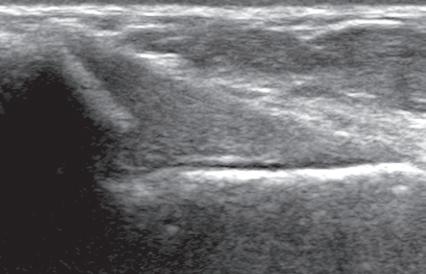

FIGURE 1.11 Anisotropy. Ultrasound images of distal supraspinatus tendon in long axis (S) shows an area of hypoechoic anisotropy (curved arrow) (A), where the tendon fibers become oblique to the sound beam, which is eliminated (B) when the transducer is repositioned so that the tendon fibers are perpendicular to the sound beam. H, Humerus.